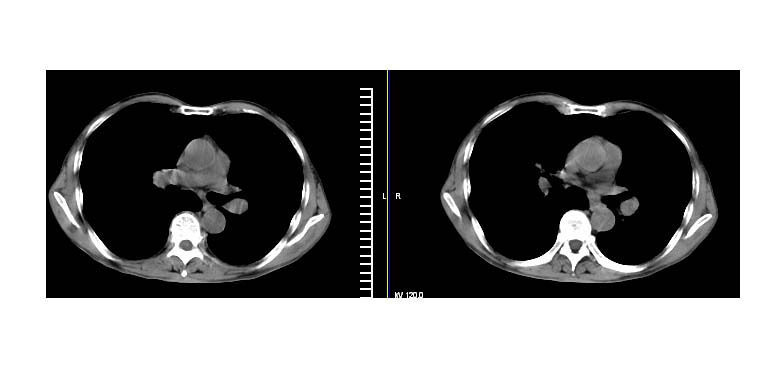

标题: CT11019:男性,66岁。发烧5-6天。治疗后无明显好转。 [打印本页]

标题: CT11019:男性,66岁。发烧5-6天。治疗后无明显好转。

阻塞性肺炎并不张,建议抗炎治疗后复查或增强

左下肺中心性肺癌伴下肺不张及周围阻塞性炎症

左下肺中央型肺癌伴阻塞性肺炎\\肺不张可能性大,建议支纤镜检查

考虑左肺下叶炎症合并叶间裂积液,建议抗炎治疗后复查

左下肺中心性肺癌伴下肺不张及周围阻塞性炎症,

建议:支气管镜检查。

左侧胸廓偏小,左下梭形高密度影,考虑阻塞性肺炎.

左肺门下分增大见有结节影,基底干及分支显示不清,下叶体积缩小,呈片带状机磨玻璃样影显示。支持考虑左下肺中心型肺癌伴阻塞性肺炎及部分肺不张。建议纤支镜检查